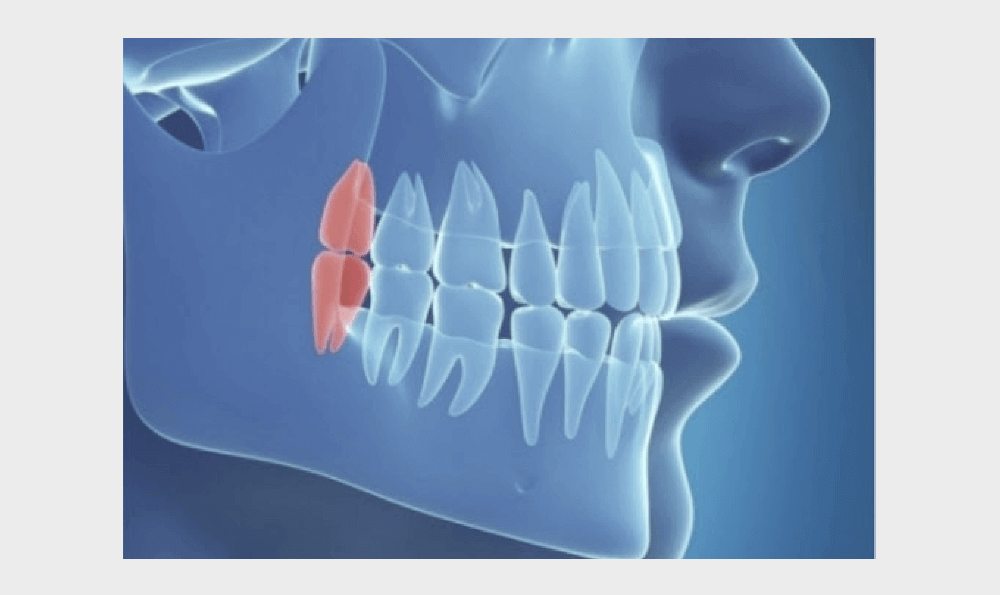

Длительность заживления зависит от сложности операции: простой, сложной или атипичной (например, когда зуб мудрости был расположен в челюсти под углом, и его пришлось удалять прямо из кости). Однако, в итоге все зависит от внимания пациента к собственному состоянию, и следования рекомендациям хирурга-стоматолога из клиники Осадчего.